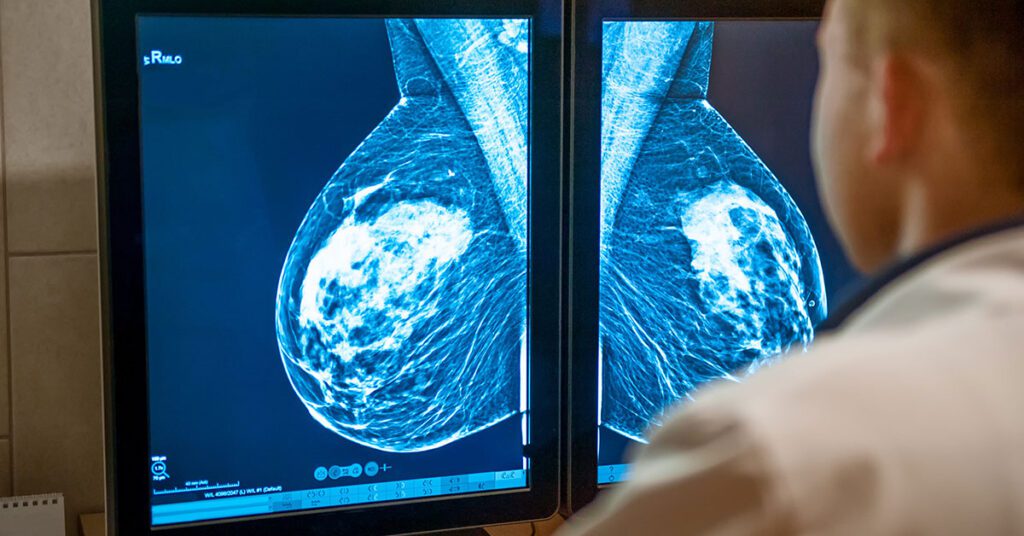

Uma nova inteligência artificial pode detectar o câncer de mama 5 anos antes de ele se desenvolver - Escola de Lucifer

Que bom que se pode usar ferramentas de IA para detectar anormalidades com eficiência ajudando na prevenção de câncer de mama, assim facilita a tratamentos antecipados. LPN